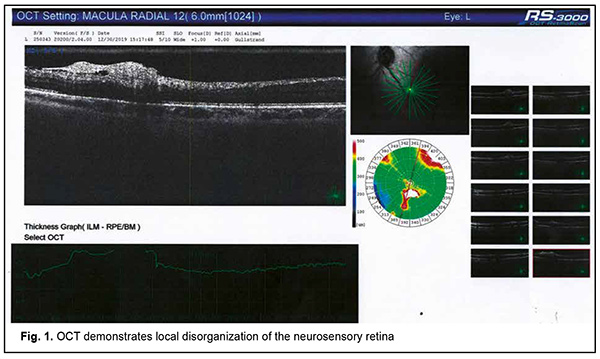

Autoimmune uveitis is a severe progressive immune inflammatory ocular disease, which can lead to rapid loss of visual function if not treated promptly [1]. Recently, advances have been made in the treatment and our understanding of the mechanisms of the disease. It has been found that the disease may be induced by microbial triggers under conditions of immunosuppression. Herpes viruses occupy a special place among the microbial triggers that can promote the breakdown of immune tolerance with the development of autoimmune uveitis [2]. Since these opportunistic agents are re-activated in the body of an immunocompromised individual through decreased immune surveillance, assessing immune status for finding the causative immune deficiency is an important component of rational diagnostics in such cases [3, 4]. It should be taken into account that it is not only secondary immune deficiencies, but also primary immune deficiency diseases, including genetically determined minor immune deficiencies, that can cause herpes virus reactivation from persistence in biological reservoirs [5]. Therefore, it is reasonable to use a three-component approach to a diagnosis of autoimmune uveitis: (1) verification of uveitis itself, (2) identification of the trigger which provoked an autoimmune response to ocular autoantigens, and (3) the diagnosis of causative immune deficiency which contributed to reactivation of the trigger and caused alterations in the mechanisms of maintenance of immune tolerance in the human body. This may ensure development of a comprehensive approach to the treatment of autoimmune uveitis with simultaneous systemic effects on all the main components of disease pathogenesis, thus not only suppressing the autoimmune response against ocular autoantigens, but also removing the reactivated microbial trigger and compensating for the immunodeficiency disease which has mediated the development of ocular lesions through decreased immune surveillance for the trigger and support of immune tolerance to host antigens [6]. Here we report a case demonstrating our multidisciplinary triple-component approach to the diagnosis of patients with autoimmune uveitis, which takes into account the main components of disease pathogenesis, thus enabling the development of an effective comprehensive approach to treatment. A female patient, born in 1967, presented to the ophthalmologist with complaints of progressive bilateral loss of vision and transient ocular pain. It was known from her history that she had been ill for the last 5 years. The disease had a waxing and waning course with short periods of remissions changed by exacerbations. The patient was diagnosed with autoimmune uveitis of the right eye in early disease and with autoimmune uveitis of the left eye, two years later. By the time of presentation, she had undergone three courses of plasmapheresis and several courses of systemic and topical corticosteroid therapy, with some transient improvements in her condition. In addition, she had undergone an episode of macular edema of the right eye. Moreover, in the presence of hormonal therapy, she had several times developed severe conjunctival blepharitis, which required administration of antibiotics in addition to glucocorticosteroids. At presentation, her best-corrected visual acuity (BCVA) was 0.4 in the right eye and 0.6 in the left eye. She exhibited bilateral signs of early corneal and lens opacification, with decreased transparency of the vitreous and fibrous vitreous strands in both eyes. Optical coherence tomography of the left eye demonstrated focal changes in the paramacular retinal area (Fig. 1, panel 3). A focus of disorganized inner retinal layer was seen in a series of scans in the region of the inferotemporal vascular arcade. The contour, structure and differentiation of the inner neuroretinal layers appeared altered. A dense and partially disrupted vitreoretinal interface was seen.